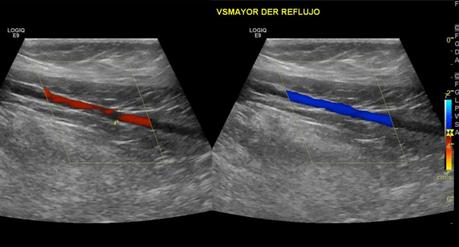

El sistema venoso superficial se observa con presencia de reflujo a la aplicación doppler a nivel de la vena safena mayor y vena safena menor.

• INSUFICIENCIA VENOSA SUPERFICIAL DE VENA SAFENA MAYOR Y VENA SAFENA MENOR, CON ALGUNAS VENAS ACCESORIAS EN TERCIO INFERIOR DE LA PIERNA.